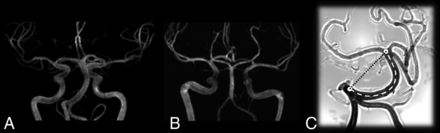

Our retrospective, transversal, case-control MRA study quantitatively investigated the morphologic basilar artery lumen changes (Fig 1) by applying a comprehensive panel of measurements encompassing all aspects of vessel dolichoectasia (diameter, length, and tortuosity) on a large cohort of patients with FD, aiming to provide a detailed picture of FD-related basilar artery changes according to age and sex.

MIP of an MRA study in A, a 41-year-old male patient with FD and B, a control patient. Note a mild increase of the tortuosity of the basilar artery and a more evident increase of the lumen diameter (compare the basilar artery with the contiguous ICA) C, Drawing of a tortuous basilar artery showing the real curved length (dashed line) and the linear distance between the basilar artery extremes (dotted line).

This index is equal to 0 when the vessel is perfectly straight, and the index increases with the relative increase of the curved length with respect to the linear length (Fig 1C).